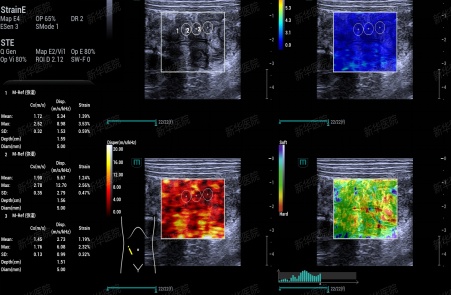

2、超声剪切波弹性成像技术:通过实时、定量、可视化地显示肠壁的软硬度,反映肠壁的僵硬程度或纤维化程度,辅助评估IBD药物治疗的疗效,如肠壁硬度增加,则提示其对药物治疗反应不敏感,通常需要手术进一步治疗;还可以辅助判断肠腔狭窄类型,炎症性狭窄还是纤维性狭窄,对后续治疗方式的选择尤为重要。

超声剪切波弹性成像实时无创定量评估肠壁软硬度